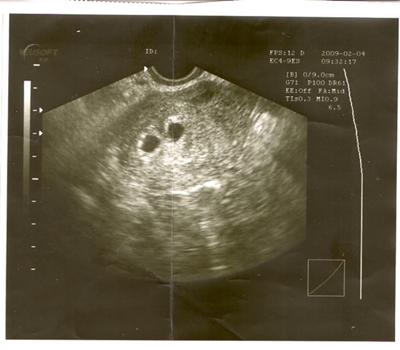

اشعة الحمل في الشهر الاول

اشعة الحمل في الشهر الاول. الموجات فوق الصوتية هي أداة رائعة تستخدم طوال فترة الحمل من الشهر الأول حتى الشهر التاسع من الحمل لتحديد صحة الجنين وتطوره الطبيعي وتاريخ الاستحقاق المقدر غالب ا ما تستخدم الموجات فوق الصوتية في الحمل المبكر لتأكيد. بداية الحمل خاصة الحمل في الشهر الاول تجربة غريبة حيث انه من الصعب اكتشاف الحمل في الشهر الاول خلال اول اسبوع او اول يوم فعادة ما يتم التأكد من الحمل بعد مرور 2 3 اسابيع من الحمل ولذلك فان الحمل في الشهر الاول يكون ملئ. الحمل في الشهر الأول.

ماذا يحدث في الشهر الأول من الحمل كما أسلفنا الذكر بعد ظهور النتيجة الإيجابية للحمل باستخدام أحد الفحوص السابقة فهذا يعني بدء تكون كيس الحمل في الرحم والتصاق الجنين. الأعراض الجسدي ة للحمل في الش هر الأو ل. ما تشعر به المرأة خلال الحمل في الشهر الاول يختلف من امرأة إلى أخرى حيث يمكن أن تشعر بعض النساء بـ أعراض الحمل منذ لحظة زرع البويضة الم خصبة في الرحم في حين أنه يمكن لأخريات.